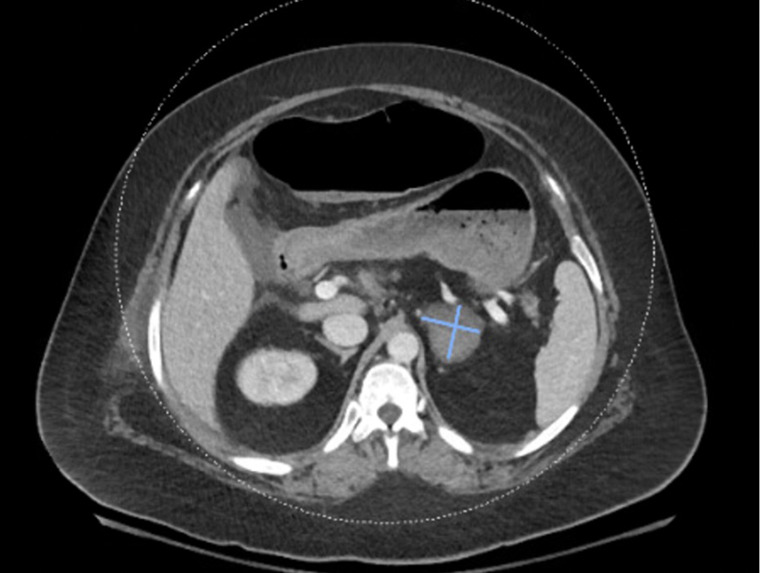

Case description: A 31-year-old female with a medical history of autism spectrum disorder, antiphospholipid syndrome (APS), complete systemic lupus erythematosus (SLE), and Evans syndrome was admitted for cholecystitis requiring laparoscopic cholecystectomy. In the setting of her acute illness, her thrombocytopenia worsened. Her hospital course was then complicated by the development of a left adrenal hematoma and venous thrombosis. Anticoagulation therapy was conservatively held due to concern for bleeding risk with the hematoma. However, given persistent thrombocytopenia, she subsequently underwent a platelet transfusion and was started on a 5-day course of intravenous immunoglobulin (IVIG). A venous Doppler ultrasound revealed a new occlusive deep venous thrombosis in the right axillary and brachial veins and occlusive venous thrombosis in the left cephalic veins while on the conservative anticoagulation regimen. This led to the immediate restart of anticoagulation therapy with close monitoring of coagulation labs. Her platelets improved Eltrombopag and IVIG up to 50,000 platelets/mcL.